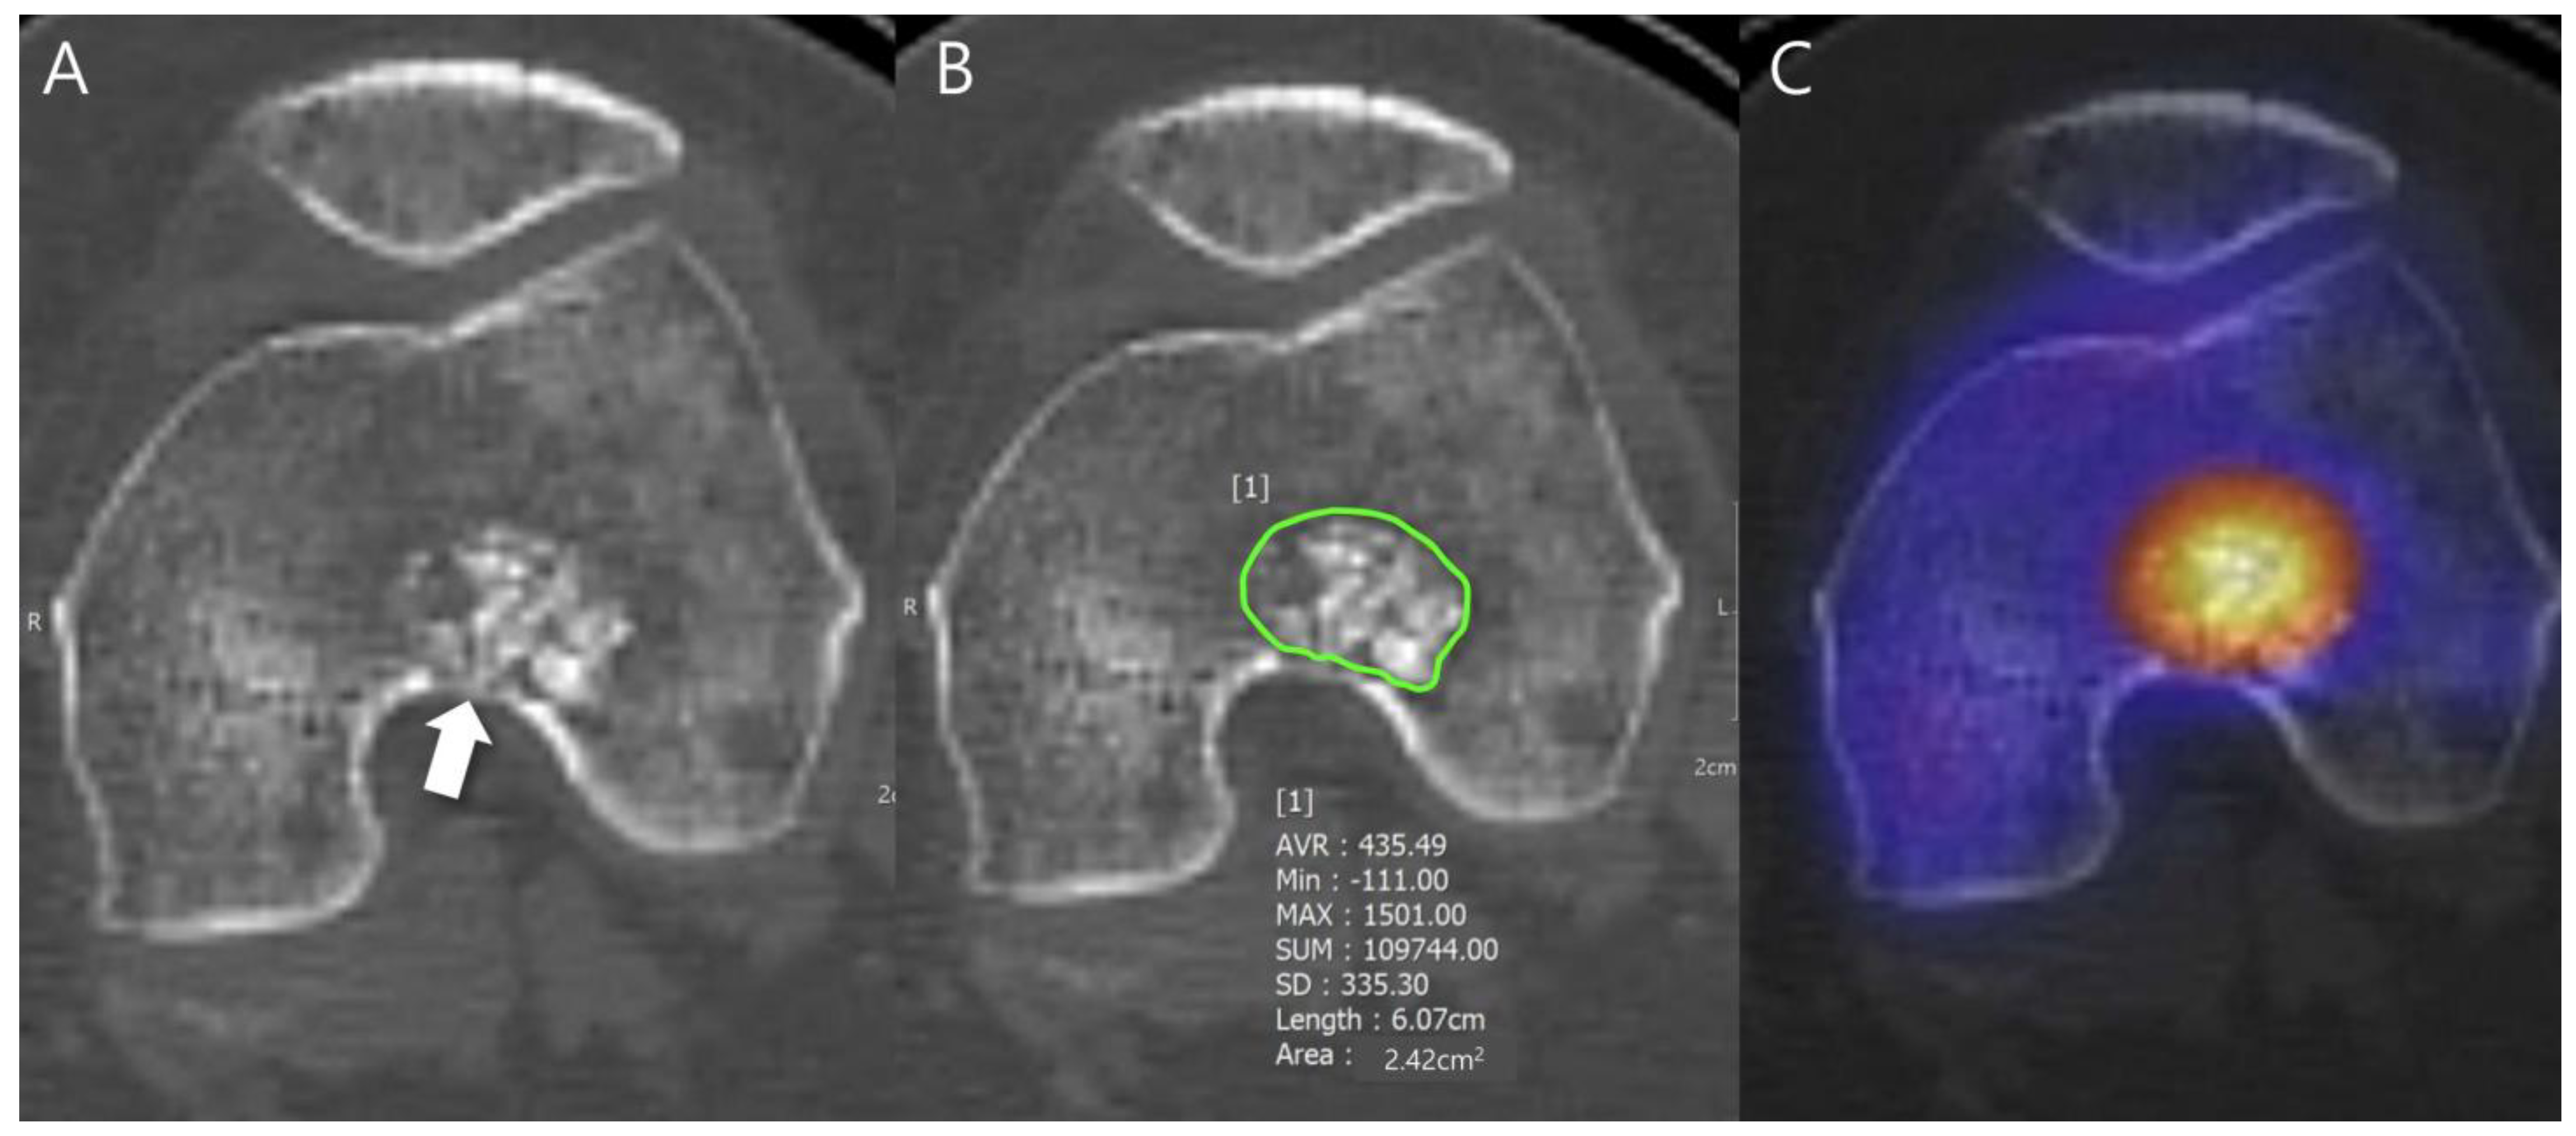

Any aggressive CT features for the grading of central cartilaginous bone tumors including (i) deep endosteal scalloping ≥ 2/3 of the normal cortical thickness (Figure 1), (ii) extensive endosteal scalloping ≥ 2/3 of the lesion length (Figure 2), (iii) expansile cortical remodeling (Figure 3), and (iv) cortical destruction with or without soft tissue extension (Figure 4) were also evaluated. The CT images were evaluated in conjunction with the plain radiographs and/or MRI. After finishing the independent review, a consensus review of the CT was performed. The two radiologists reviewed the CT images together to reach a final consensus on discrepant interpretations from the independent reading.

Figure 2. Extensive endosteal scalloping ≥ 2/3 of the lesion length in a patient with ACT in the distal femur. (A) An axial CT image shows a lobulated mass containing chondroid matrix mineralization and focal endosteal scalloping (arrow). (B) A sagittal T2-weighted image shows a lobulated mass with heterogeneously increased signal intensity and extensive endosteal scalloping ≥ 2/3 of the lesion length (arrows).